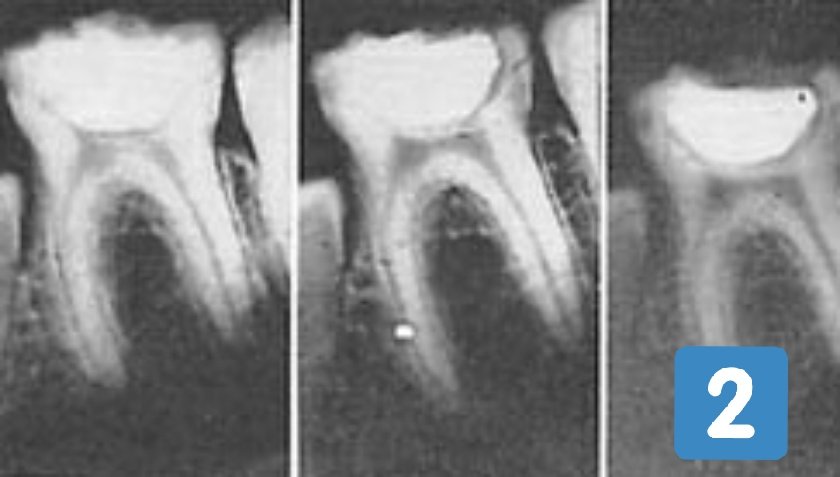

الأرقام أسفل توضّح الأجزاء الرئيسيّة للسن:

١ - الطبقة الطلائيّة.

٢ - الطبقة العاجيّة.

٣ - الغرفة اللُبِّية.

تبدأ المشاكل في الغالب، من تكوين متكرّر للصديد والتهابات وعدوى بكتيريّة وآلام مستوجبة لإزالة أعصاب عند تمكّن النخور من الوصول للغرفة اللُبِّية وتعريضها للمحيط الخارجي.

الأشعّة السينيّة للأسنان في الصور ٢،١ و٣ أسفل هي لثلاثة أطفال من مناطق مختلفة، عاشوا تحت بيئة غذائية متجانسة سيّئة، من محاصيل وزيوت نباتيّة، طحين وموارد مستوردة مع حد الأطعمة الحيوانيّة.

النخر من سوس الأسنان تمكَّن من الطبقة الطلائيّة والعاجيّة للسن ليبدأ كشف الغرفة اللُبِّية.

بعد رصد المحقّق للثلاث حالات، وقبل أي إجراء جراحي لأسنان الأطفال الثلاثة، هدَف برايس إلى معرفة أثر التغذية في هذه المرحلة المهمّة من حياة السن.

أخضع المحقّق الأطفال لبرنامج غذائي تُسجّل فيه تفاصيل التحليل الكيميائي للّعاب مع مكان وحجم وعمق النخر، لفترة زمنية قصيرة من أربعة أشهر.

البرنامج الغذائي المرسوم من المحقّق للثلاثة أطفال ارتكز على تغذية حيوانيّة شبه خالصة، متينة بمصادر الفيتامينات والمعادن والأحماض.

المتابعة الأسبوعية من المحقّق للثلاث أسنان أثناء البرنامج الغذائي الخاص للأطفال، تقصَّت إبداع الخَلْق الإلاهي وكماله، في قدرة أنسجة الغرفة اللُبِّية من إنشاء طبقة جديدة ثانويّة عاجيّة، حالت دون كشف الطبقة اللُبِّية من النخور للمحيط الخارجي، لتُجهض بذلك داعي جراحة معالجة الأعصاب!

تتابعت المفاجآت لبرايس عند تدوين التحسّن اللحظي بعد دخول البرنامج لمركّبات، معادن وإنزيمات اللّعاب من التحليل الكيميائي الدوري.

بعد أن كان التحليل الكيميائي للعاب يرمي إلى عامل أمان ضعيف جدًا، محفِّز لتنشيط سوس السن للنخر، أصبح العامل قوي جدًا ومستحكَم، معيق لاستمراريّة التسوّس.